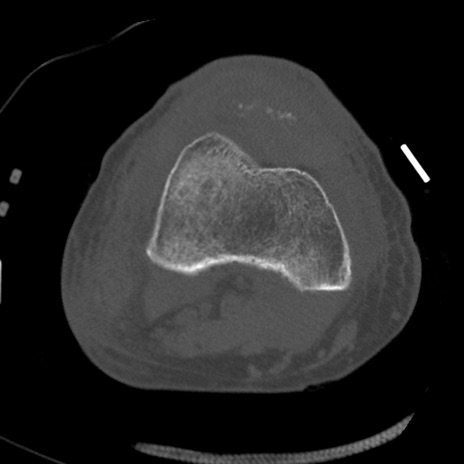

症例28 右膝関節CT(横断像)

右膝関節CT